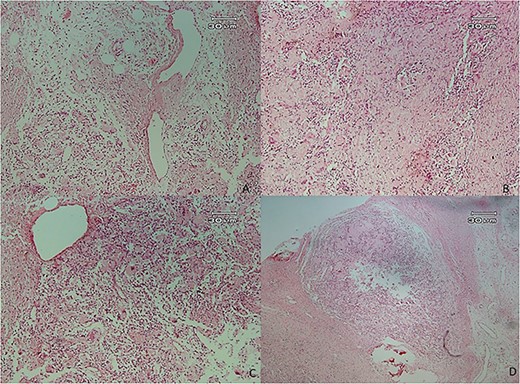

Microscopic examination showed (Figs 4–7) inflamed connective tissue composed of prominent plasma cells mixed with numerous osteoclastic multinucleated giant cells of various sizes with intracytoplasmic asteroid bodies and round Schaumann bodies, which surrounding round to amorphous eosinophilic areas composed of the spindle to stellate cells in fibromyxoid background is also evident.

Histopathologic views of the lesion (H&E staining, ×100 magnification). Inflamed fibromyxoid connective tissue and foreign body giant cells.

Histopathologic views of the lesion (H&E staining×100 magnification) showing chronic inflammatory cells admixed with multinucleated giant cells of varying sizes.